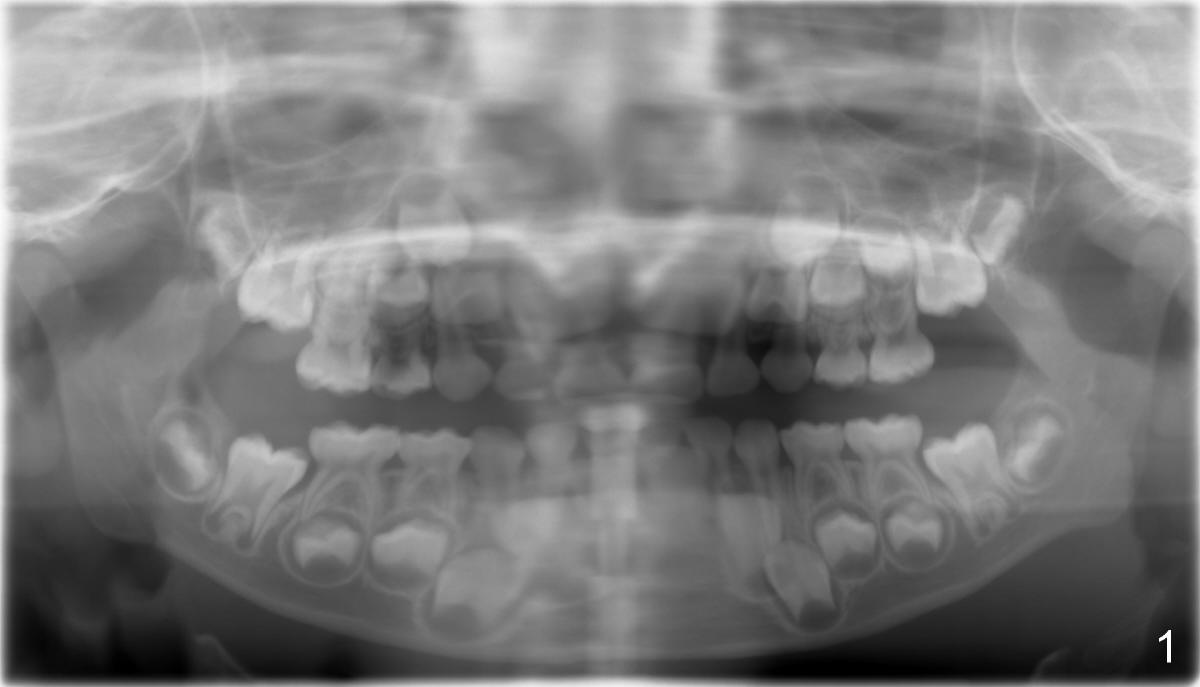

Panramic X-ray was taken when Edward was 6 years 5 months old (Fig.1). His parents and he himself found that the upper right lateral did not erupt at the age of 9 years 2 months (Fig.2-4: *). Gingivectomy was performed using soft tissue laser to expose the incisal edge of the lateral. Five months later, the lateral has erupted partially (Fig.5-8), but the family is concerned about the cosmetic issue. It appears that the upper midline has shifted to the right (Fig.6). Periapical film is planned to take to confirm the relationship between the canine and the lateral.